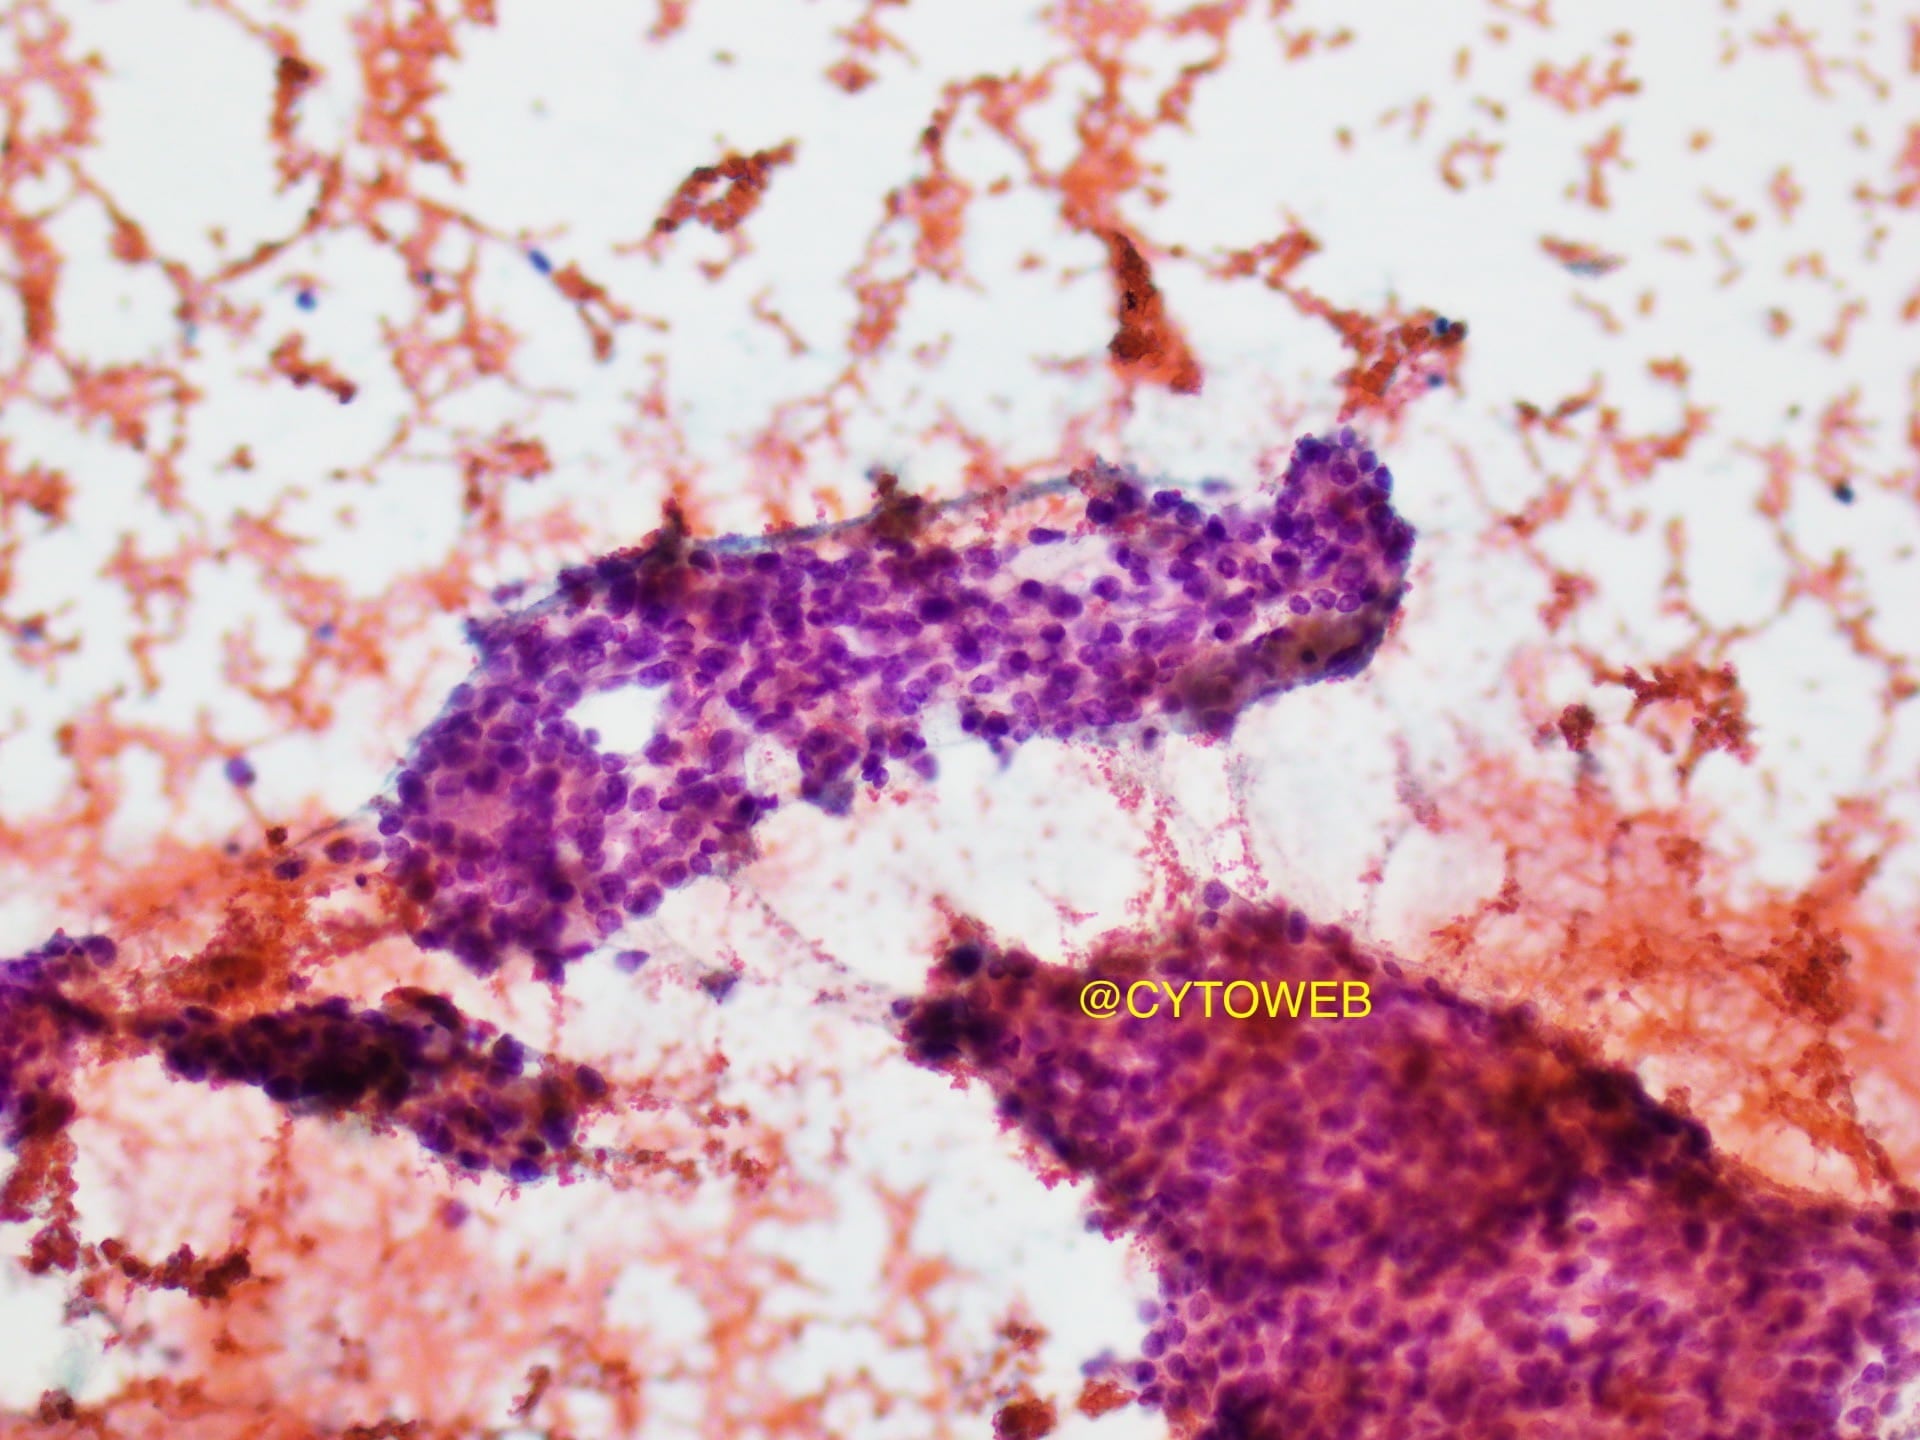

- Crowded sheets of tumour cells with overlapping nuclei

- Acinar formation is discernible within the sheets

- Round to oval eccentric nuclei with mild nuclear pleomorphism

- Fine powdery chromatin and inconspicuous nucleoli

- Clean background – no necrosis